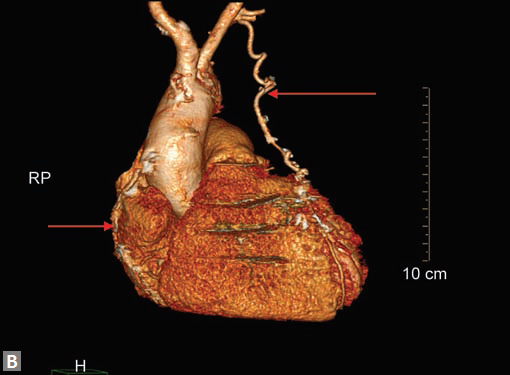

CT is the preferred tool of investigation of coronary bypass grafts (Fig. 9). Reversed saphenous vein grafts (SVGs) are optimally studied consistently. Anastomotic sites are studied effectively. However, distal anastomosis of venous graft to obtuse marginal branch (OM) is relatively difficult to evaluate because of diminishing caliber of native vessel. Arterial grafts pose a small challenge due to artifacts of associated surgical clips (Figs 10A and B). Ostium and proximal part of graft are assessed well. However, distal anastomotic site may be difficult to assess on occasions. RIMA graft, posterior descending artery (PDA) graft, gastroepiploic artery graft can also be studied. Stenosed venous grafts

can be stented and the same can be evaluated by CT (Fig. 11). Like native RCA, RCA grafts (Figs 12A and B) are more susceptible to motion artifacts when compared to LAD and OM grafts. Catheter angiogram can be used to answer specific queries after CT angiogram.